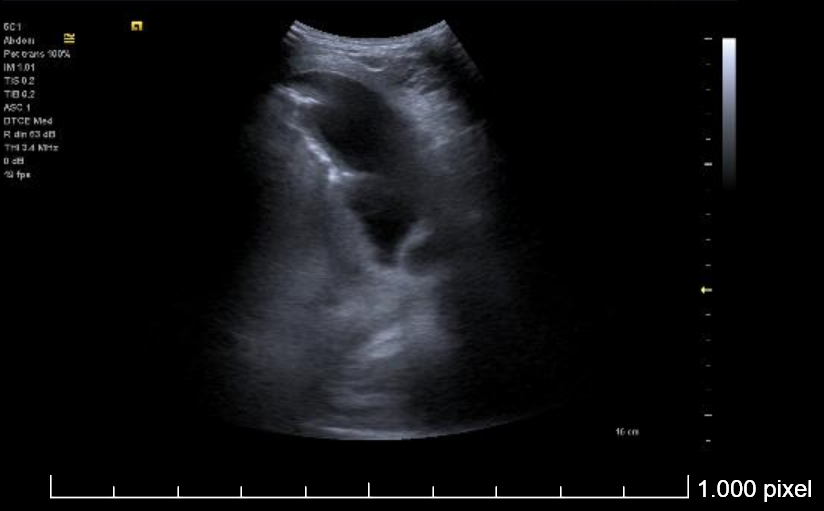

Ecografía torácica:

Derrame pleural izquierdo de 4 espacios intercostales, libre, hipoecogénico, sin ecos internos. Lóbulo pulmonar inferior izquierdo con imagen de patrón mixto (Intersticial y consolidación).

Se realiza toracocentesis diagnóstica y evacuadora con la paciente en decúbito lateral derecho. Se drenan un total de 550 cc en total de LP serohemático (pH en gasómetro 7.58).